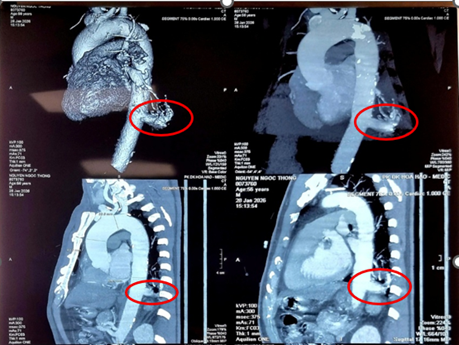

Theo thông tin từ bệnh viện, bệnh nhân N.N.T (56 tuổi, Tây Ninh) tình cờ phát hiện tổn thương ở thùy dưới phổi trái khi khám sức khỏe tổng quát. Qua thăm khám và chẩn đoán chuyên sâu, các bác sĩ xác định ông mắc phổi biệt lập nội thùy với khối tổn thương kích thước 23 x 26 mm. Đáng lưu ý, động mạch nuôi khối này xuất phát trực tiếp từ động mạch chủ ngực xuống, có đường kính lên đến 17 mm – kích thước lớn, tiềm ẩn nguy cơ vỡ mạch và chảy máu ồ ạt nếu không được xử trí kịp thời.

ThS.BSCKII Nguyễn Văn Việt Thành – Trưởng khoa Ngoại Lồng ngực – Bướu cổ – cho biết, thách thức lớn nhất trong ca mổ là phẫu tích nhánh động mạch nuôi bất thường. Mạch máu này có kích thước lớn, thành mạch dễ tổn thương và dính chặt do tình trạng viêm mạn tính xung quanh. Chỉ một sai sót nhỏ cũng có thể gây biến chứng chảy máu nghiêm trọng, khó kiểm soát.

Các chuyên gia khuyến cáo, nếu có biểu hiện viêm phổi tái diễn tại cùng một vị trí, ho ra máu hoặc phát hiện bất thường ở phổi qua khám sức khỏe, người dân nên đến cơ sở y tế chuyên sâu để tầm soát. Các phương tiện chẩn đoán hình ảnh như MSCT có thể giúp phát hiện sớm phổi biệt lập và kịp thời xử trí.